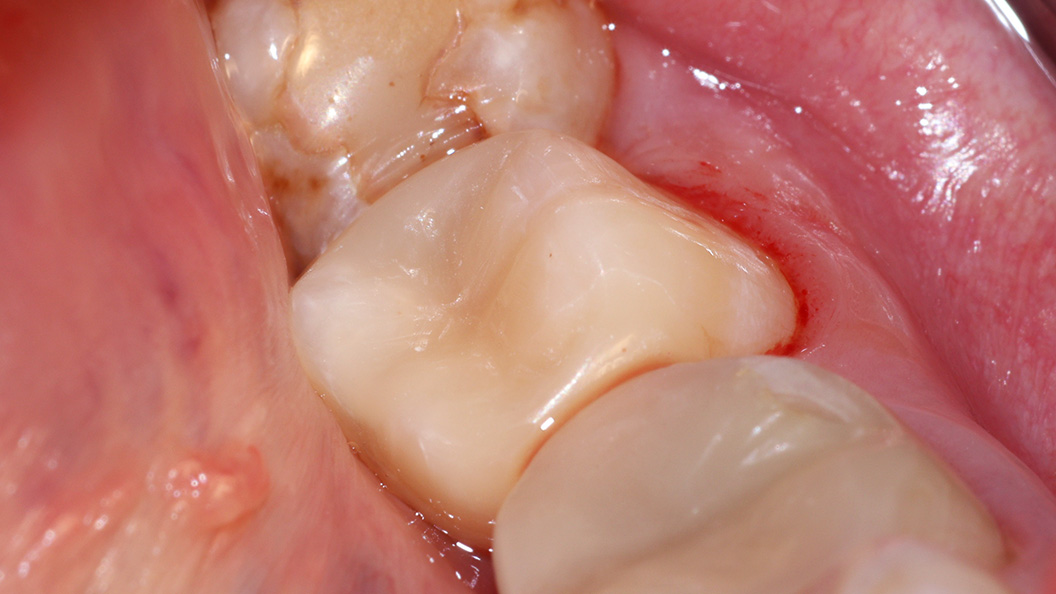

В ходе лечения были проведены следующие мероприятия:

- механическая и медикаментозная обработка кариозной полости;

- пломбирование с применением светоотверждаемого композита Estelite;

- проведено микроконтурирование и макроконтурирование пломбы.